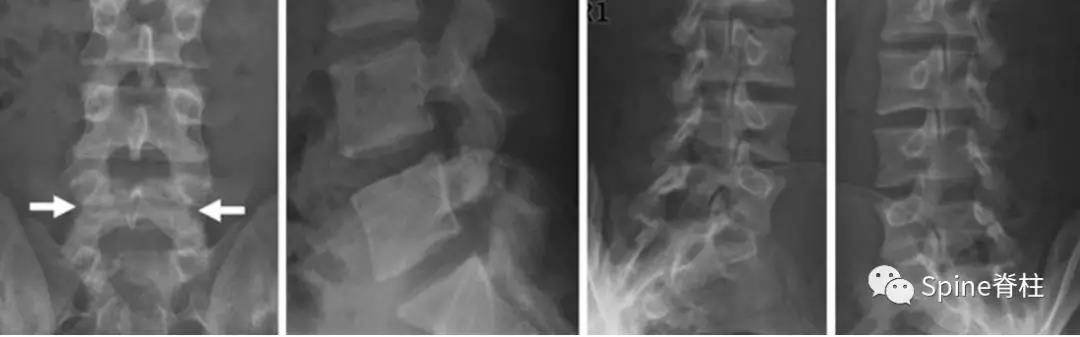

图:6个月复查可见右侧椎弓根裂已愈合(单箭头),但出现右侧峡部裂(双箭头)